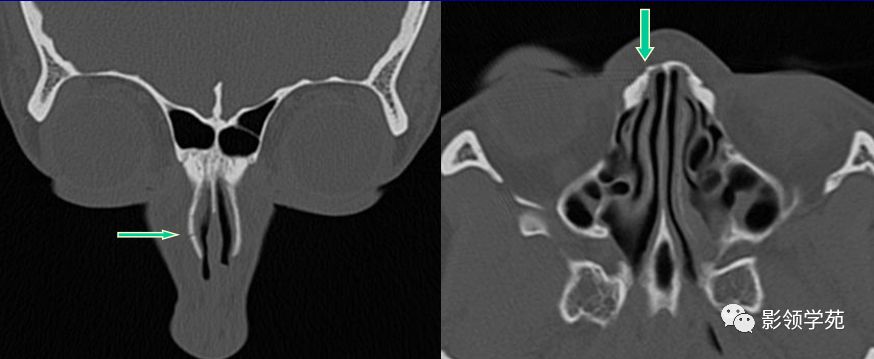

线性骨折 粉碎骨折

右侧鼻骨线形骨折

鼻骨线形骨折